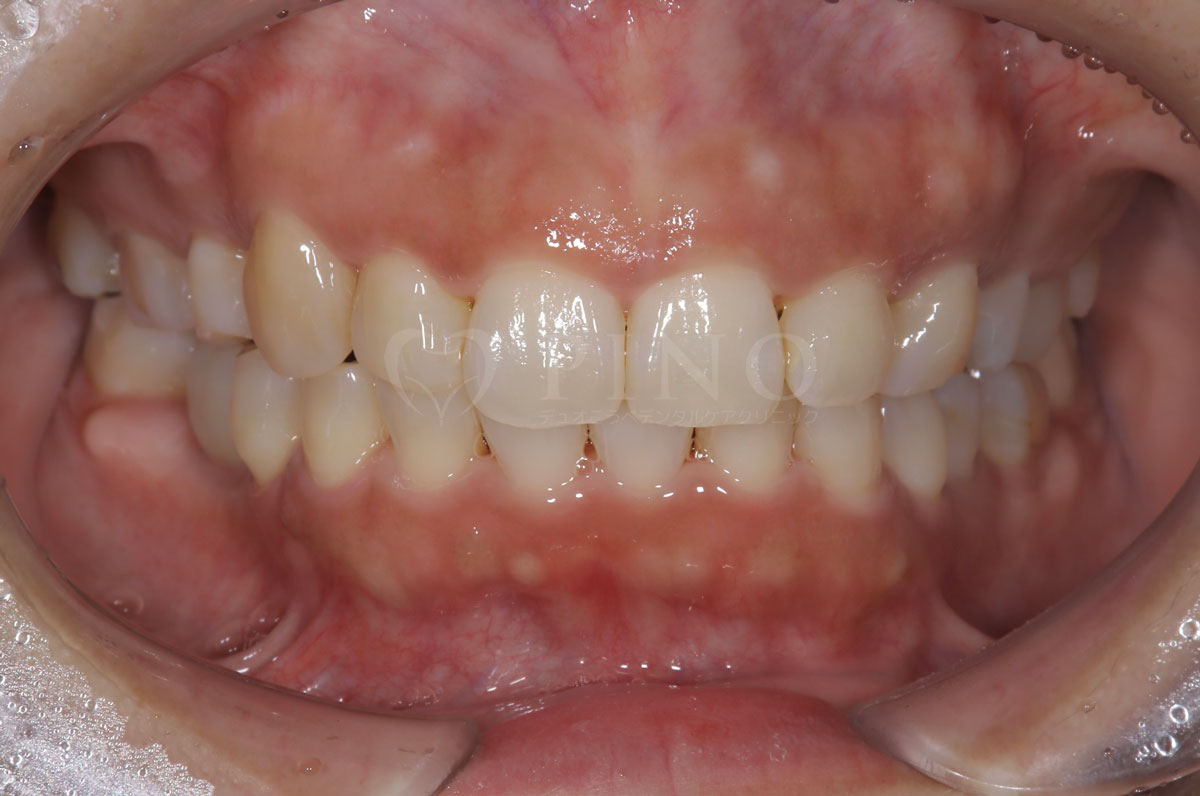

症例2:ワイヤー矯正後の後戻りが気になる(50代女性)

主訴 ワイヤー矯正後に後戻りが気になる 診断名 叢生 治療方法 マウスピース部分矯正 抜歯 なし オルソパルス なし 治療期間 10ヶ月 費用 436,000円+補綴費用360,000円 副作用・注意点 矯正後の後戻りを防ぐためリテーナーの使用が必要となる 備考 1年4ヶ月で補綴も完了した -